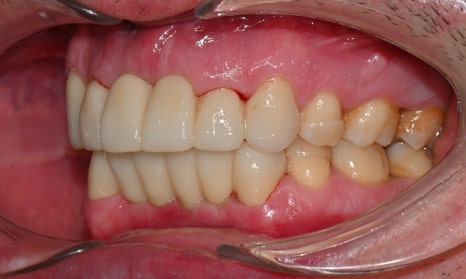

2026-1-7 최종 보철물 장착 : 연세정원치과

치료가 모두 마무리된 후, 환자분의 미소는 이전과 비교해 전반적으로 한층 더 안정적이고 조화로운 인상으로 개선되었습니다. 앞니의 길이, 형태, 배열이 아랫입술 곡선을 따라 형성되는 smile arc와 자연스럽게 조화를 이루면서, 웃을 때 과도한 긴장감 없이 부드러운 심미적 균형을 회복할 수 있었습니다. 기능적인 교합 안정성과 함께 심미적인 만족도 역시 높게 나타났으며, 환자분도 결과에 대해 매우 만족해하셨습니다.